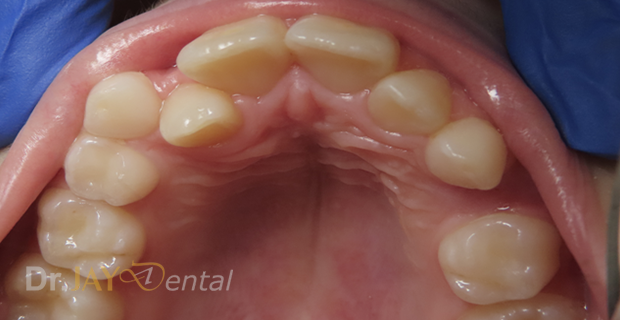

Patient had issue with spacing needed for erupting teeth , patient still going through treatment. After picture : in 6 months with Myofunctional therapy and tongue tie revision , jaws are widening and teeth are having space to erupt

Before

After